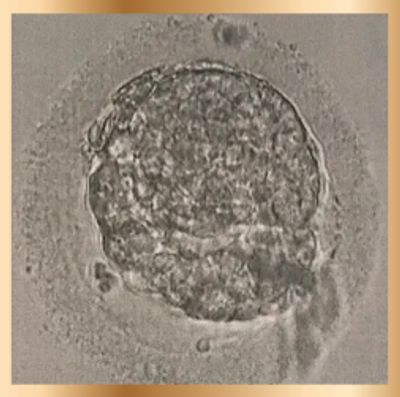

My first attempt at the new clinic failed, as no changes were made. However, they then did an ERA test, checking whether the embryo transfer timing was correct. They do a biopsy of your uterus, put you through a mock IVF cycle, and do blood tests. I was also then allowed to try intralipids, believed to help with immune issues and went for genetic testing of the embryos to heighten my chances of having healthy embryos and lessen the number of further embryo transfers.